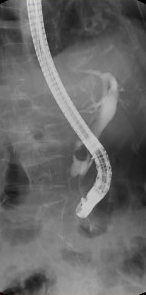

| 内視鏡的逆行性 胆道膵管造影(ERCP) |

内視鏡(胃カメラ)を使った造影検査です。 |

![]() 内視鏡的逆行性胆道膵管造影(ERCP) |